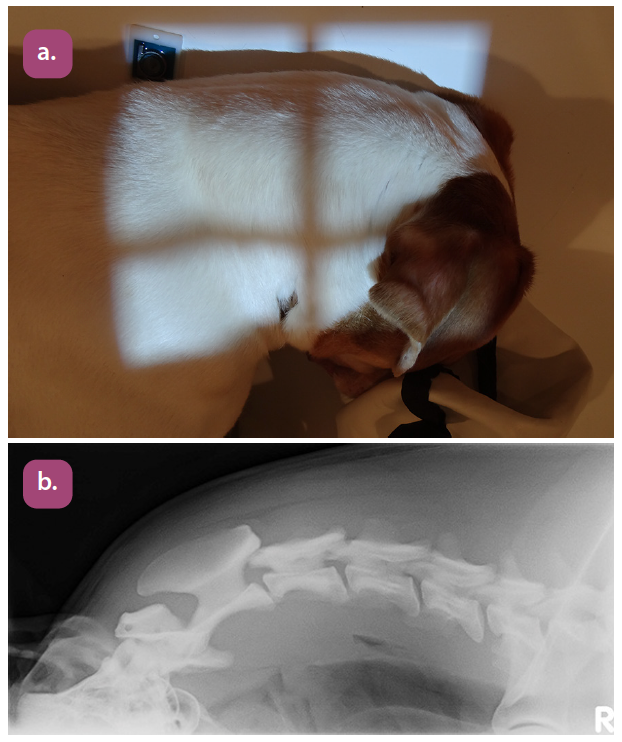

lateral cervical spine projection

lateral cervical spine extended projection

lateral cervical spine flexed projection